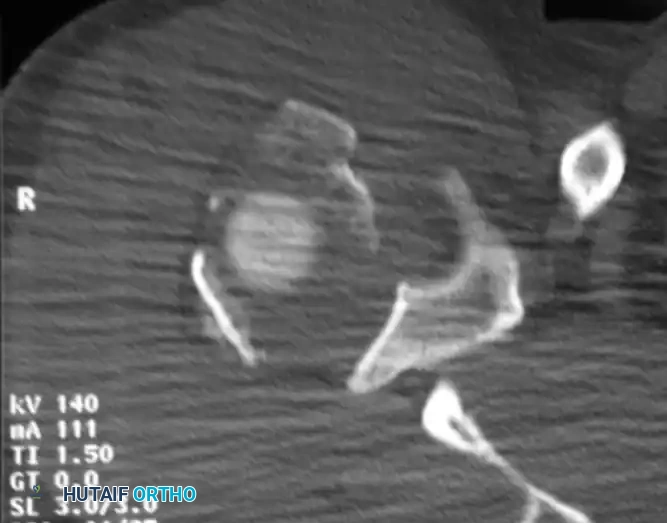

التصوير المقطعي المحوسب

في حالات الكسور المعقدة أو عندما تكون الإزاحة بين أجزاء العظم غير واضحة في الأشعة السينية العادية، يلجأ الطبيب إلى التصوير المقطعي المحوسب. يوفر هذا الفحص صوراً ثلاثية الأبعاد عالية الدقة، مما يساعد الجراح في التخطيط الدقيق للعملية الجراحية وتحديد حجم وموقع كل قطعة عظمية بدقة متناهية.

إليك بعض الصور الإشعاعية والرسوم التوضيحية الإضافية التي توضح أشكال التثبيت الجراحي المختلفة لكسور أعلى عظمة العضد